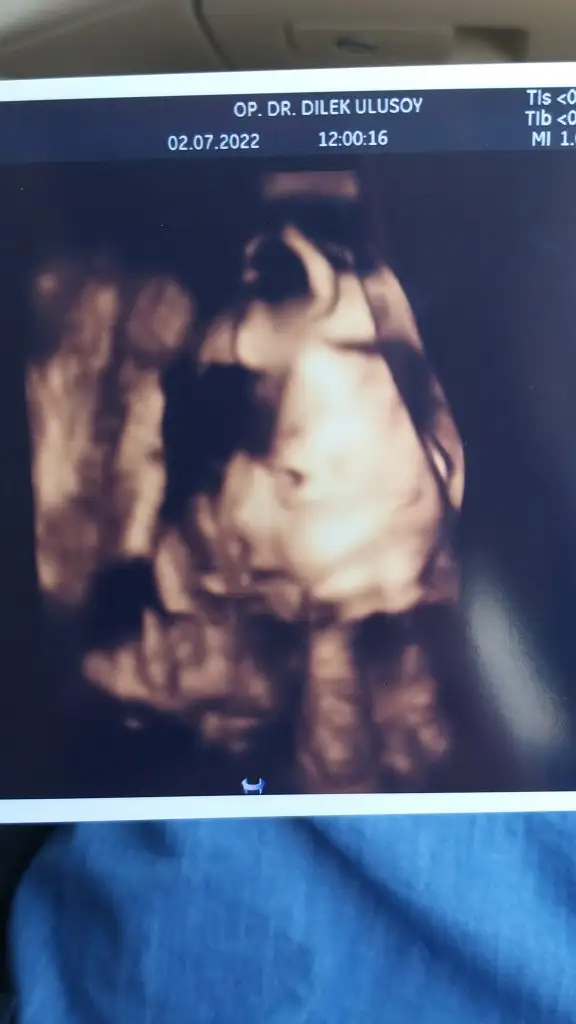

Merhaba annişler bizim bugün kontrolümüz vardı Keremim büyümüş 28 hafta 2 günlük bugün, bikaç gün önde çıktı gelişimi 1 kilo 258 gram olmuş 39 cm 💙 Baş aşağı dönmüş bile bizimki ama doktorumuz sorun yok daha yer değiştirir rahim ağzı güzel dedi, önden yine göstermedi kendini yandan profil alabildik 😊 32.haftadada nts istedi artık sancı kontrollerimizde başlıyor hayırlısıyla🤩

Eklentiler

• IMG-20220702-WA0000.webp

IMG-20220702-WA0000.webp

16,1 KB · Görüntüleme: 85